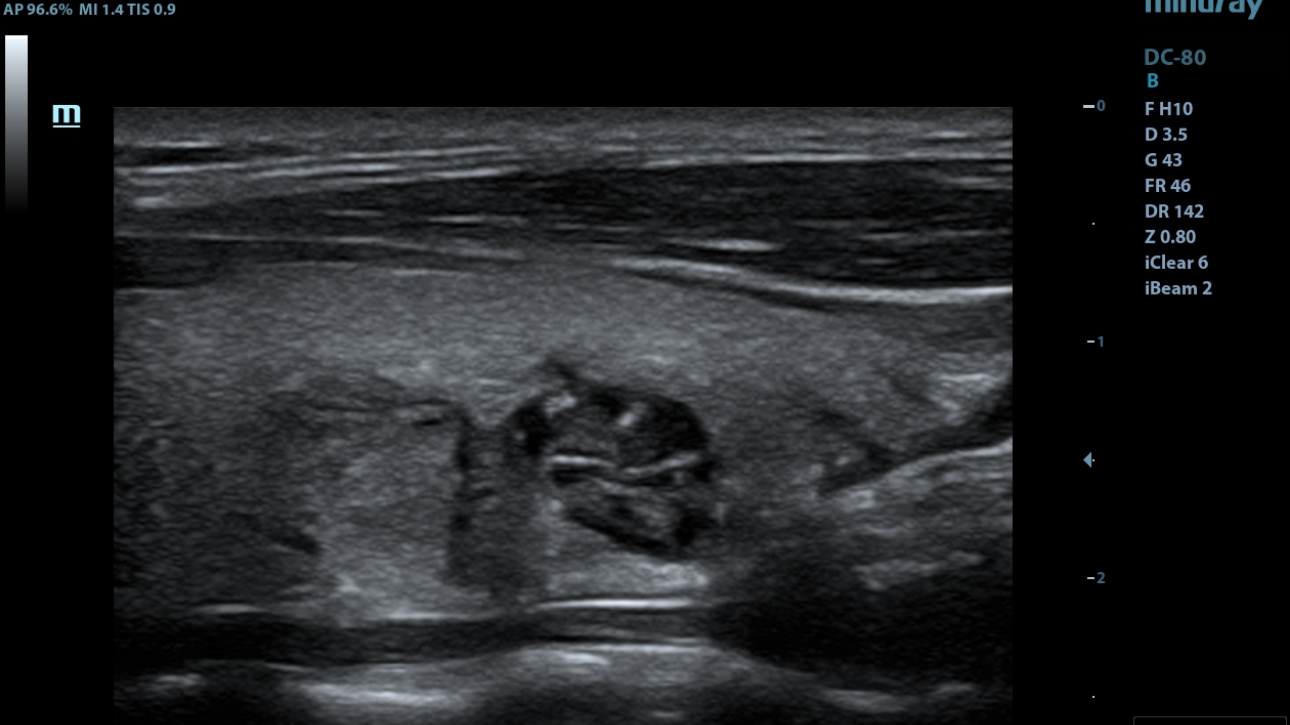

iNeedle

ItŌĆÖs the 2nd generation needle enhancement technology with automatic angle adjustments for easy needle approach to target and enhanced accuracy during guided procedures.